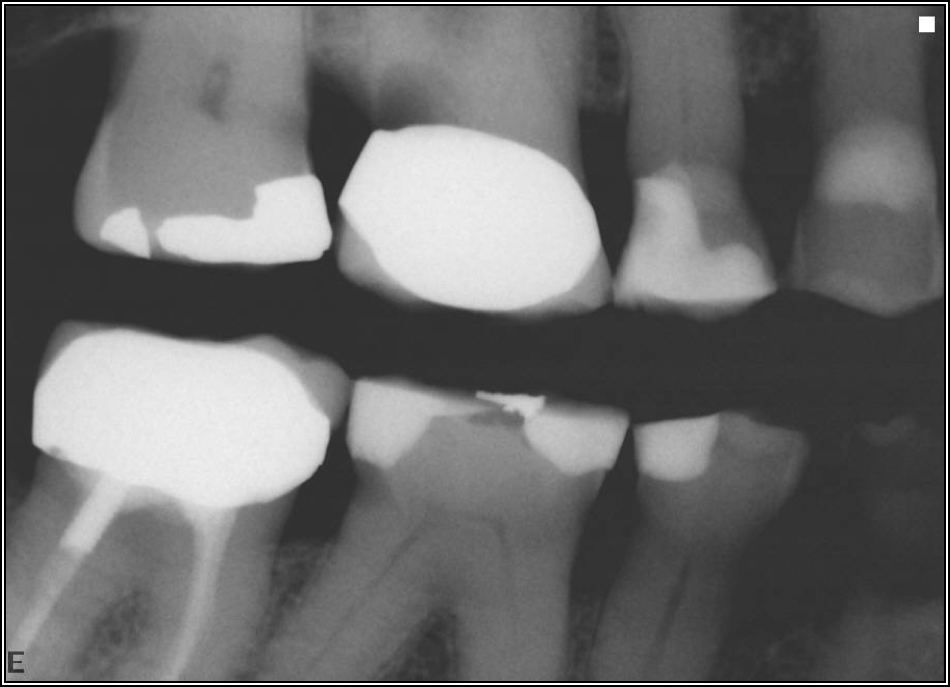

Occlusion is one of the most overlooked areas in endodontics; however, other than remaining structure, it is the most important factor.7 Patients who are heavy bruxers can cause the need for a root canal from the lateral forces. Patients who clench pose a different challenge with apical forces, yet the damage from both can be the same. Figure 7 shows a patient with bruxism. The patient had pain in response to hot and cold stimulus, and the clinicians needed a bitewing to determine which tooth was causing the pain. From the periapical (PA), it was clear that tooth No. 2 had a large problem, No. 3 had a crown, and No. 4 had a large restoration. Any of the three may have been the source of the problem.

With the bitewing shown in Figure 8, it became clear there was gross decay in tooth No. 3 that could not be seen on the PA, and there was a periodontal defect, a pulp stone, in No. 2. There was also a class V lesion revealing the bruxism, flat occlusion, multiple restorations in No. 30, a post in No. 31, and decay on No. 2 as well. The post in No. 31 was useless because when a post is placed, it must be the right length, width, and size. If the post is too short, there will be a greater fulcrum and the tooth will break. If it is too long, the clinician can break it by wedging it. If it is too short, it will not hurt the tooth, but it will not provide any valuable function. It is overall preferable to do posts in teeth having just single restorations rather than abutments for bridges because those teeth are already under greater force. If the technique is not performed correctly, iatrogenic issues may result.

Fig 7. Bruxism.

Figure 7

Fig 8. Bitewing revealed decay and other problems.

Figure 8